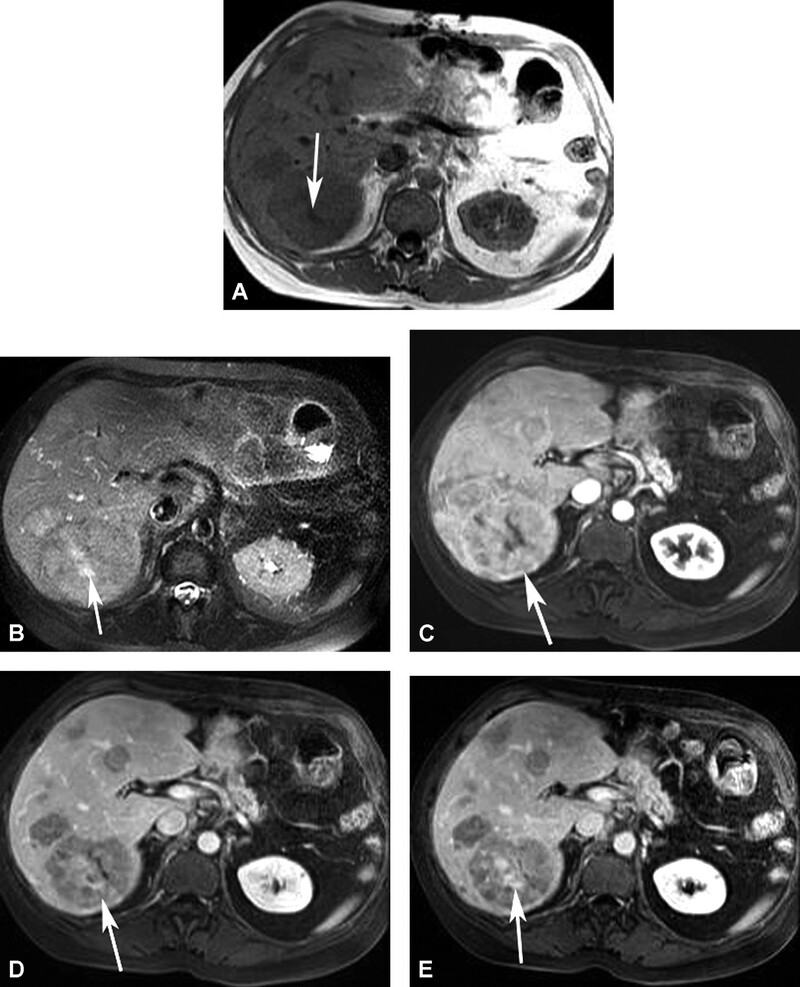

Hemangioma là u gan lành tính thường gặp nhất. Hemangioma thường gặp ở phụ nữ trẻ và 15-20% nhiều ổ. Mô học cho thấy một loạt các hồ máu và kênh mạch, các tổn thương lớn hơn tạo ra các vùng huyết khối và xơ. Siêu âm thấy một khối tăng âm, đồng nhất, giới hạn rõ, tăng âm phía sau yếu (Hình 1). Các tổn thương lớn hơn (>6cm) có thể không đồng nhất và giảm âm do huyết khối, hoại tử và thoái hóa nang. Các dấu hiệu CT cản quang gồm tăng quang dạng nốt ngoại vi ở thì động mạch với lấp đầy hướng tâm dần trong tổn thương ở thì tĩnh mạch cửa và thì muộn (hình 2). Vôi tĩnh mạch (phlebolith) có thể thấy trong tổn thương ở 15-20% trường hợp (Hình 2). MRI cho thấy tăng tín hiệu trung bình trên T2W, thường ít hơn so với nang đơn thuần, tín hiệu thấp trên T1W. MRI sau tiêm thuốc cho thấy bắt thuốc dạng nốt gián đoạn phía ngoại vi ở thì động mạch, đó là đặc điểm điển hình của hemangioma (Hình 3). MRI thì tĩnh mạch và thì muộn có thể thấy các nốt bắt thuốc lớn dần và hợp lưu với lấp dầy trung tâm ở các mức độ khác nhau tương tự như CT.

Hình 2. Bệnh nhân nữ 42 tuổi, hemnagioma. CT không cản quang (A) thấy đốm đóng vôi (mũi tên) ở ngoại vi khối giảm đậm độ gợi ý vôi tĩnh mạch. Có tăng quang dạng nốt ngoại vi (mũi tên ) ở thì động mạch (B), lấp vào trung tâm (mũi tên) ở thì tĩnh mạch cửa (C). Thì muộn (D) thấy lấp vào một phần tổn thương (mũi tên) do huyết khối.

Nói chung các tổn thương nhỏ hơn lấp đầy thuốc nhanh hơn các tổn thương lớn. Các hemangioma khổng lồ, thường lớn hơn 5-10cm, có thể không lấp đầy hoàn toàn thuốc tương phản (Hình 4 và 5), và có thể tạo ra các vùng nang giới hạn rõ ở trung tâm như dịc h đơn thuần. Các tổn thương nhỏ, <1cm, có thể lấp đầy nhanh và có thể không phân biệt được với HCC hoặc di căn giàu mạch máu. Tuy nhiên, u giàu mạch máu thải thuốc nhanh, trong khi hemangioma tăng quang dai dẳng do thải thuốc chậm. Ngoài ra hemangioma còn có tín hiệu cao trên T2W với thời gian echo lớn hơn 112ms, trong khi các u ác tính không thấy tín hiệu cao. Hình ảnh thì động mạch với thời gian tối ưu cung cấp thông tin chẩn đoán quan trọng nhất để xác định đặc điểm hemangioma.